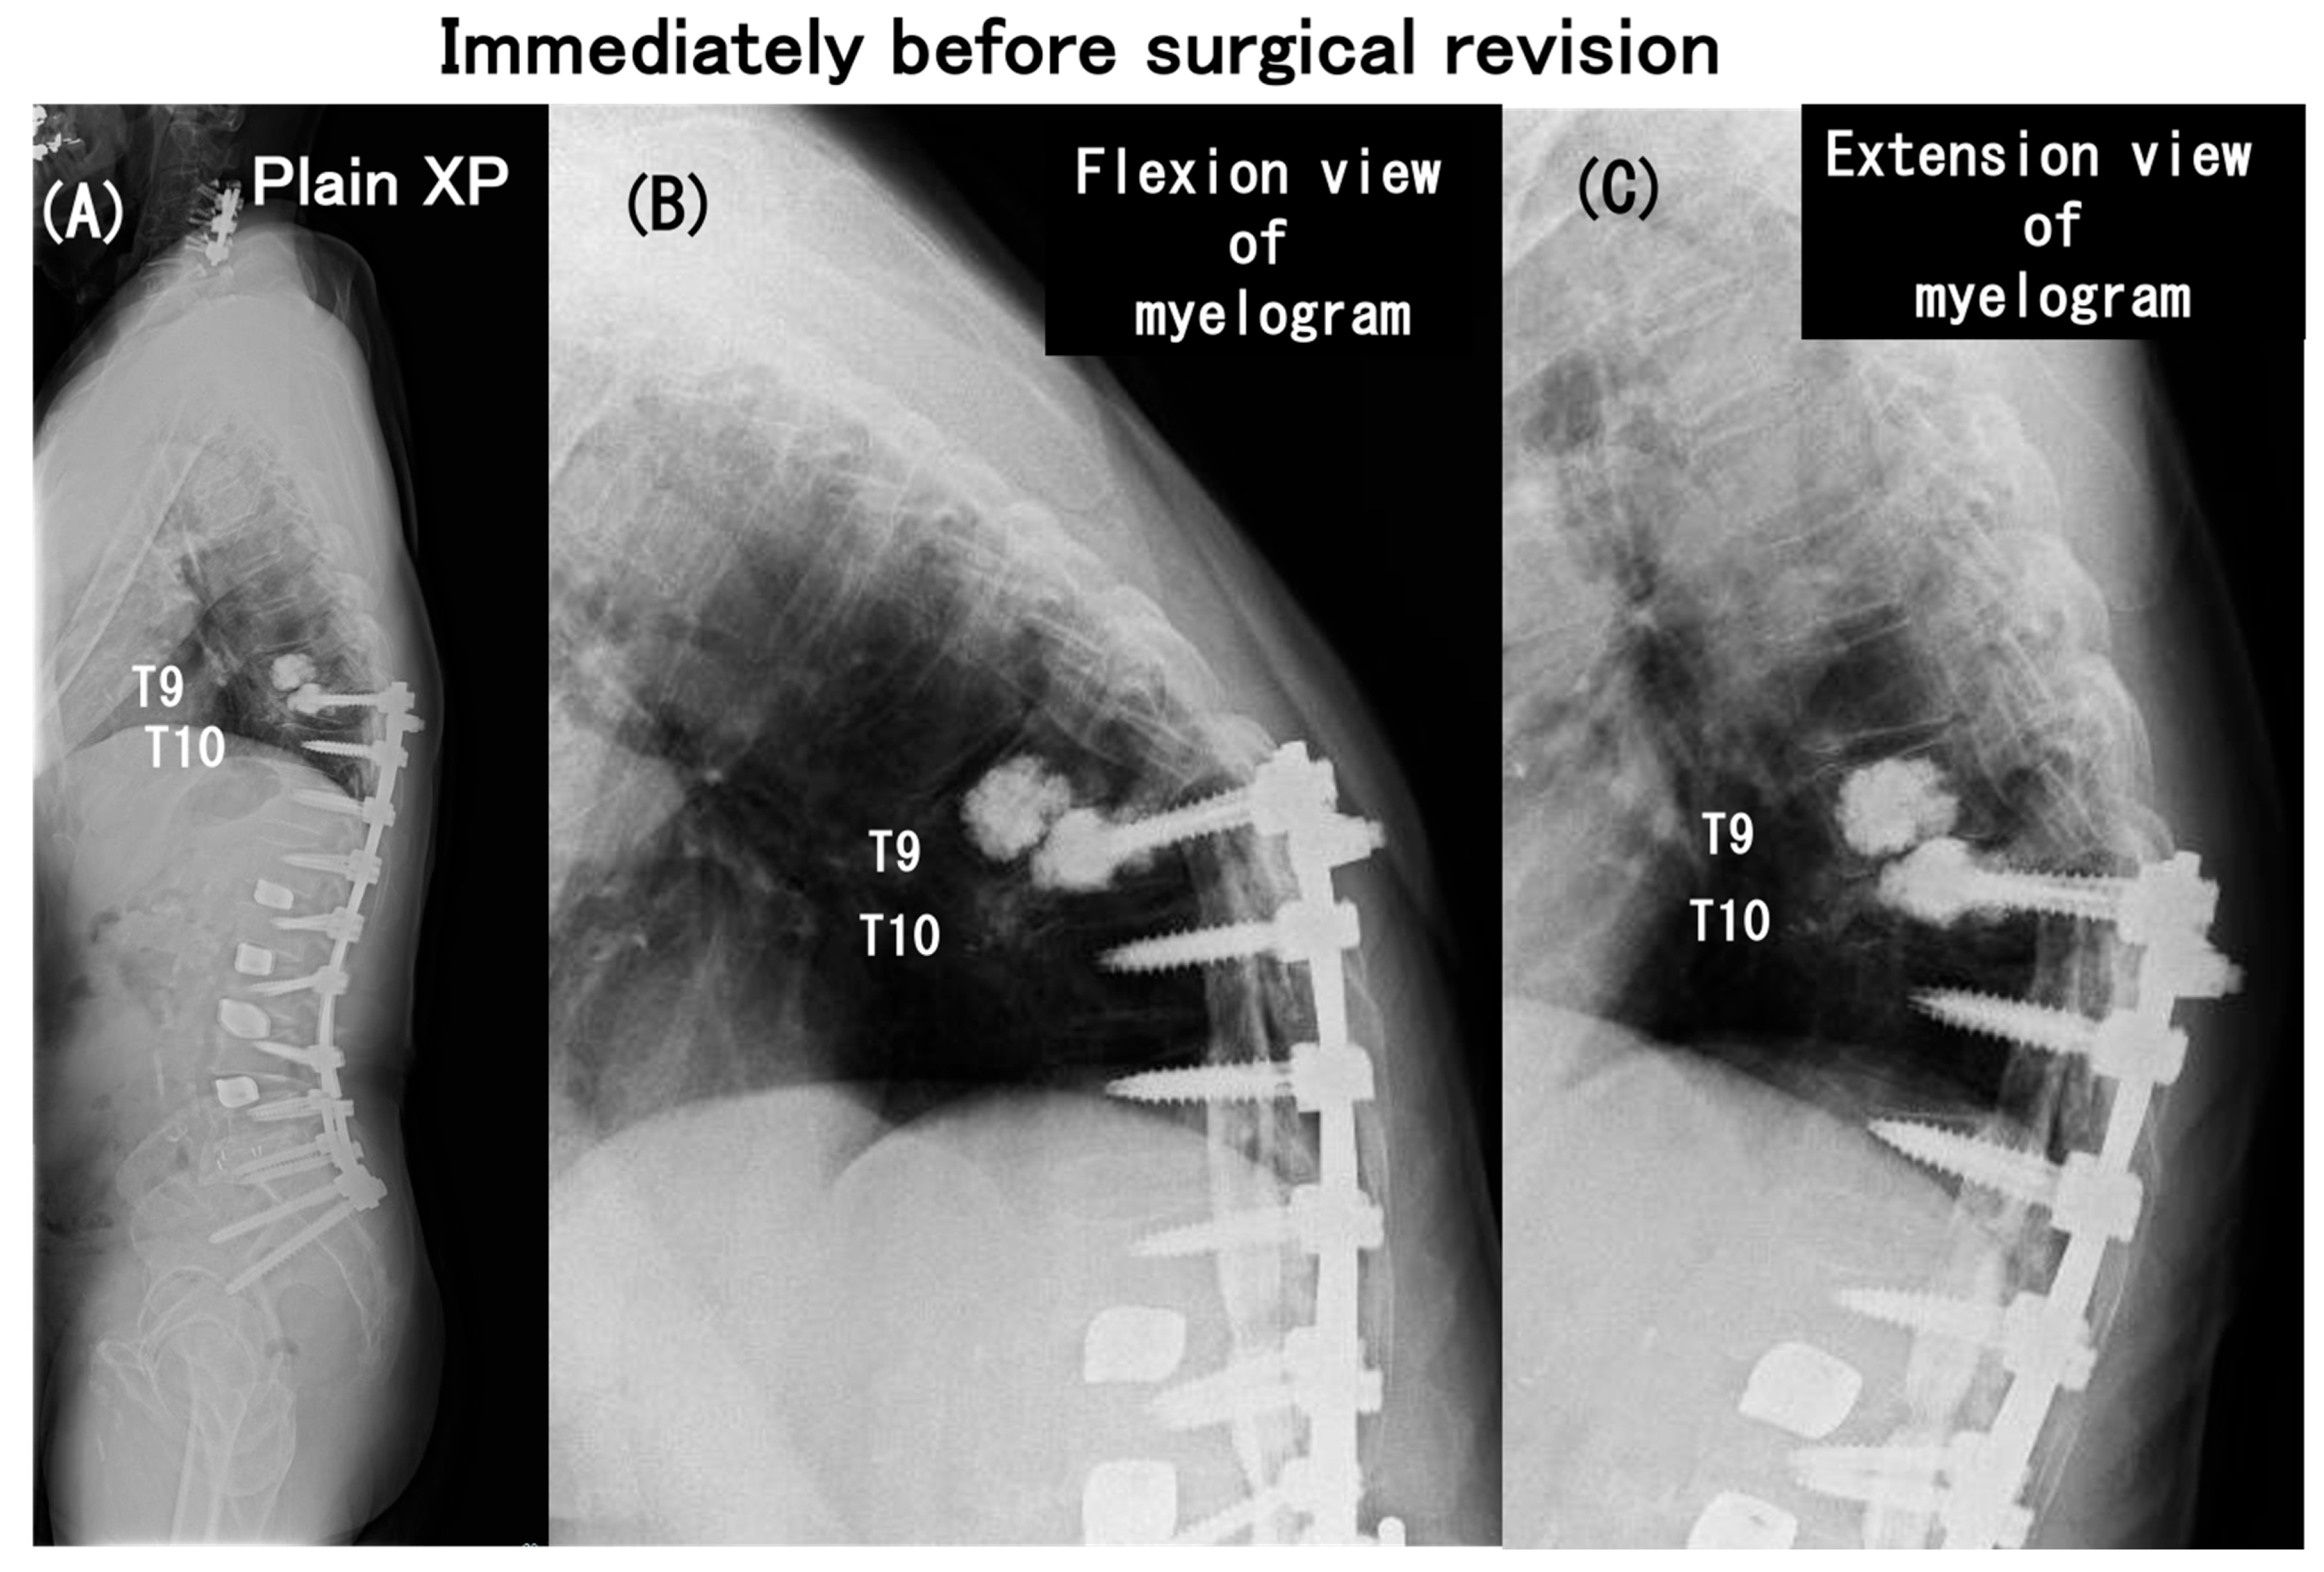

3.6. Case Presentation

- Case no. 6

- 2.

- Case no. 4